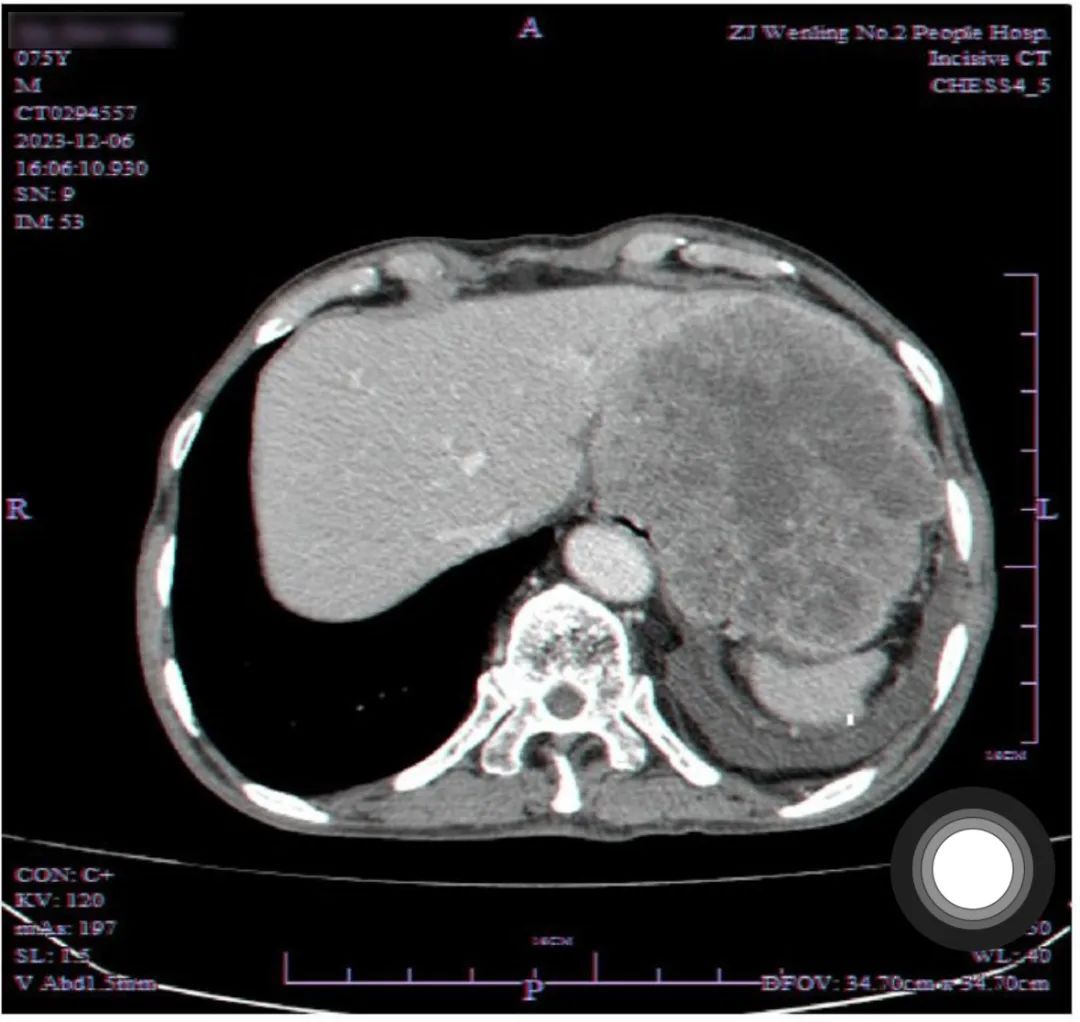

经过详细的 CT 检查,医生发现赵阿公的肝胃间隙有一个巨大的占位性病变,侵犯了胃壁并向腔内生长。这是一个极为不利的信号,意味着赵阿公的病情可能相当严重。